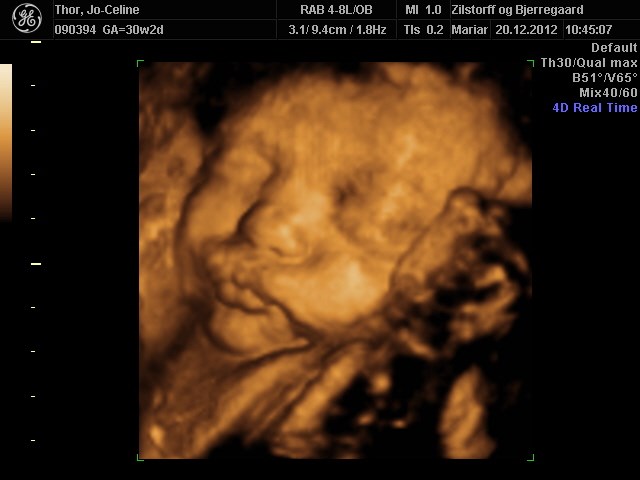

Søger man på Google kommer der kun 3D-billeder.

Så jeg vil høre om nogen herinde har et billede eller to fra uge 28 de vil vise? Og hvor lang var jeres baby, og fik I vægt at vide?